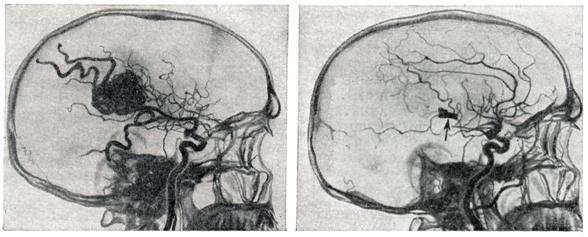

Диагноз.Появление перечисленных выше симптомов в молодом возрасте (чаще на 2—3-м десятилетии жизни) дает основание для предположения артерио-венозной аневризмы. Диагноз может быть поставлен лишь на основании всестороннего ангиографического исследования. Для выявления приводящих артерий и рано заполняющихся дренирующих вен необходима серийная ангиография с наибольшим числом снимков в первые 2—3 секунд. Лечение.Консервативное лечение является по существу симптоматическим и заключается в применении противосудорожных препаратов: фенобарбитал, дилантин и другие. При кровоизлияниях необходимо проведение коагулянтной и гипотензивной терапии. Лучевая терапия при артерио-венозных аневризмах неэффективна. Радикальным методом лечения является полное иссечение артерио-венозной аневризмы (рис. 4). Однако при большой распространенности аневризм и их расположении в глубинных, жизненно важных структурах мозга такая операция может оказаться невыполнимой. В подобных случаях могут применяться операции, уменьшающие приток крови к аневризме или приводящие к частичному выключению аневризмы,— окклюзия приводящих артерий, эмболизация артерио-венозной аневризмы и некоторые другие. Показания к той или иной операции должны быть строго индивидуальными; они определяются особенностями клинического течения, в частности количеством и тяжестью перенесенных кровоизлияний, локализацией, распространенностью аневризмы, характером ее кровоснабжения и опытом хирурга. В связи с совершенствованием техники операций, в частности широким использованием микроваскулярпой техники, показания к радикальному удалению артерио-венозных аневризм ставятся более широко, в том числе и при аневризмах, располагающихся в функционально важных зонах (речевой, двигательной). При радикальном удалении крупных, богато васкуляризируемых аневризм операцию следует начинать с выключения приводящих артерий. Благодаря этому уменьшается кровенаполнение аневризмы, а следовательно, меньше кровопотеря. При небольших поверхностно расположенных артерио-венозных аневризмах допустимо первоначальное выключение дренирующей вены; аневризма при этом наполняется кровью и более четко контурируется. Удаление аневризм, особенно расположенных в функционально важных областях, следует производить, выделяя сосудистый клубок по границе с мозгом, оставляя на поверхности аневризмы лишь тонкий слой измененного мозгового вещества. Важно при этом все время манипулировать вне пределов сосудистого клубка аневризмы, поскольку повреждение целостности ее сосудов приводит к сильному кровотечению, которое трудно остановить. Наличие внутримозговых гематом облегчает обнаружение аневризмы. Иногда гематомы как бы отслаивают часть аневризмы от мозга и тем самым упрощают ее удаление. При небольших глубоко расположенных аневризмах для облегчения их обнаружения во время операции могут быть использованы принципы стереотаксической нейрохирургии. Предварительно на основании расчетов по ангиограммам в область расположения аневризмы вводится направитель, по которому затем осуществляется подход к ней. При невозможности радикального удаления аневризмы может быть применено выключение приводящих артерий. Хотя этим путем обычно не удается достигнуть излечения и спустя некоторое время развиваются новые источники кровоснабжения артерио-венозной аневризмы, такая операция может привести к ослаблению кровотока в ней и уменьшить возможность повторных кровоизлияний. При больших, богато васкуляризированных аневризмах может быть осуществлена эмболизация сосудов аневризмы с помощью рентгеноконтрастных эмболов. С этой целью обычно используются различного размера пластиковые шарики, которые вводят через обнаженную на шее сонную (иногда вертебральную) артерию. В связи с резким ускорением тока крови в аневризме эмболы устремляются в ее сосуды. Таким образом иногда удается выключить из кровообращения значительную часть артерио-венозной аневризмы (рис. 5). Выполнение подобной операции требует точных представлений о характере кровоснабжения аневризмы, о диаметре, месте отхождения приводящих артерий и прочего. Каждый этап операции нужно контролировать повторным ангиографическим исследованием. Несоблюдение этих предосторожностей может привести к попаданию эмболов в нормальные сосуды мозга. Для направленного выключения сосудов, кровоснабжающих аневризму, а также для лечения других сосудистых поражений мозга (каротидпокавернозные соустья, некрые формы артериальных аневризм) применяют так называемые ангиотаксические операции. Смысл этих операций заключается в том, что подход к пораженному участку осуществляется по кровеносному руслу внутри просвета сосуда. С этой целью используют специальные катетеры, снабженные окклюзирующим баллончиком (Ф. А. Сербиненко, 1971). Такой катетер может быть направленно введен в приводящий сосуд артерио-венозной аневризмы посредством пункции сонной артерии на шее. Конструкция катетера позволяет произвести окклюзию сосуда, оставив в артерии баллончик, заполненный быстротвердеющим пластическим веществом, а катетер извлечь (рис. 6). Делаются попытки хирургического лечения артерио-венозных аневризм путем их замораживания с помощью жидкого азота. При аневризмах большой вены мозга, вызывающих окклюзию путей цереброспинальной жидкости, если нет условий для их удаления, возникают показания для разгрузочной операции с отведением цереброспинальной жидкости из желудочков мозга в венозное русло (вентрикуло-аурикулостомия). При тотальном удалении артерио-венозной аневризмы полностью исчезает опасность повторных кровоизлияний, прекращаются или становятся реже эпилептические припадки. Наступает нормализация кровообращения в головном мозге: при контрольном ангиографическом исследовании отмечается нормализация просвета ранее расширенных артерий, не заполняются дренирующие вены, лучше контрастируются сосуды областей мозга, прилегавших к аневризме. Летальность при тотальном удалении артерио-венозных аневризм колеблется в широких пределах и определяется прежде всего показаниями для хирургического лечения. По литературным данным, средняя послеоперационная летальность составляет приблизительно 10%, но при правильном определении показаний и использовании современных хирургических возможностей могут быть достигнуты лучшие результаты.